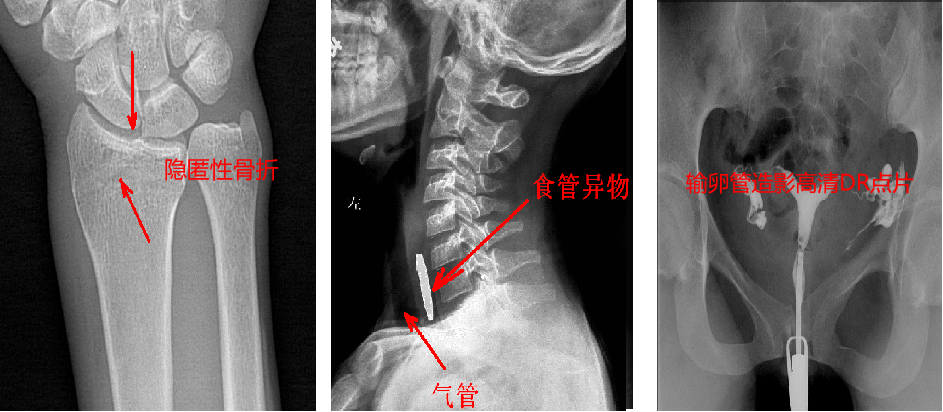

靜態(tài)DR最大的缺陷來自于盲拍,因此造成誤診發(fā)生率高,是保證診斷準(zhǔn)確性的巨大阻礙因素。在靜態(tài)拍片中,部分特殊病灶容易被遮掩而導(dǎo)致漏診,在一些特殊造影上需要憑借醫(yī)生的臨床經(jīng)驗(yàn)才能獲取有效影像。而動(dòng)態(tài)DR依靠可視化高速高清點(diǎn)片功能,改變了傳統(tǒng)的盲拍模式。動(dòng)態(tài)DR在低劑量數(shù)字透視的情況下,能夠進(jìn)行疑似病灶部位點(diǎn)片,極速精準(zhǔn)獲取有效信息,同時(shí)可即時(shí)回放視頻信息,在臨床上極大地提高了病變的檢出率,降低漏診誤診。

在功能上,動(dòng)態(tài)DR已不再局限于簡(jiǎn)單的拍片功能,而是集數(shù)字化攝影、數(shù)字化透視、數(shù)字化造影、數(shù)字化實(shí)時(shí)點(diǎn)片于一體,臨床用途廣泛,可應(yīng)用于臨床各科室,如體檢科、內(nèi)科、外科、骨科、創(chuàng)傷科、急診科等。

與此同時(shí),動(dòng)態(tài)DR的成像視野與精度也勝于靜態(tài)DR。動(dòng)態(tài) DR17×17 英寸方形幅面進(jìn)行動(dòng)態(tài)成像,能夠?qū)鹘y(tǒng)動(dòng)態(tài)造影幅面小的問題全部解決,同時(shí)由于幅面較大,臨床操作技師能夠在一個(gè)大的幅面下觀察診斷,當(dāng)看到病變部位時(shí)實(shí)時(shí)高清點(diǎn)片,從而很好地捕捉到病變點(diǎn),也大大降低了檢查時(shí)間。